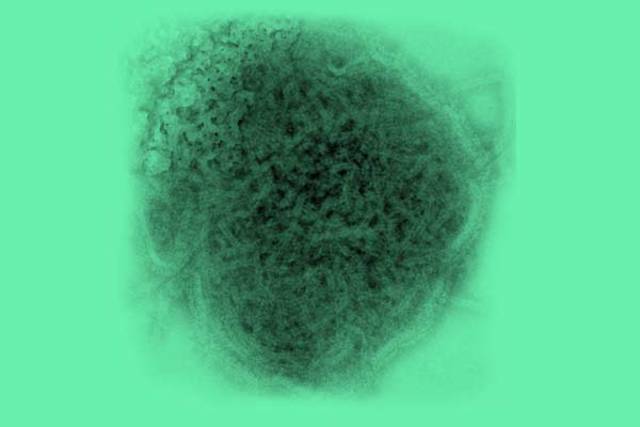

As of Dec. 9, there are 64 confirmed or probable cases of the mumps on campus. In response, the New York State Department of Health, the Ulster County Health Department, and SUNY New Paltz will hold a vaccination on Dec. 13 and 14. The school is recommending that students receive a third dose of the MMR vaccine. Students will receive the vaccination for free upon registration on my.newpaltz.edu. Photo By: Ulster County Health Department